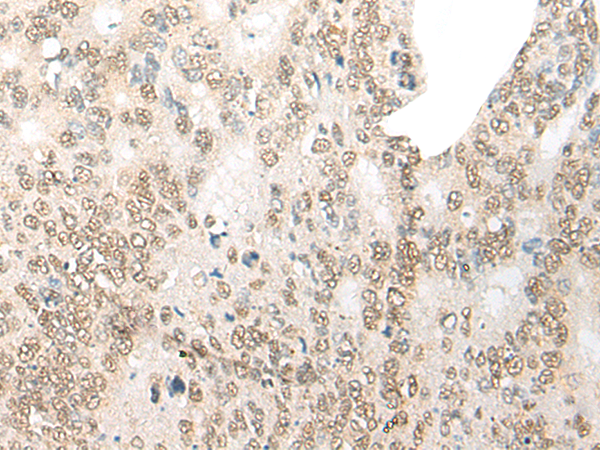

CDX4 |

caudal type homeobox 4 |

IHC positive control: |

Human gastric cancer; Human colorectal cancer |

IHC Recommend dilution: |

20-100 |